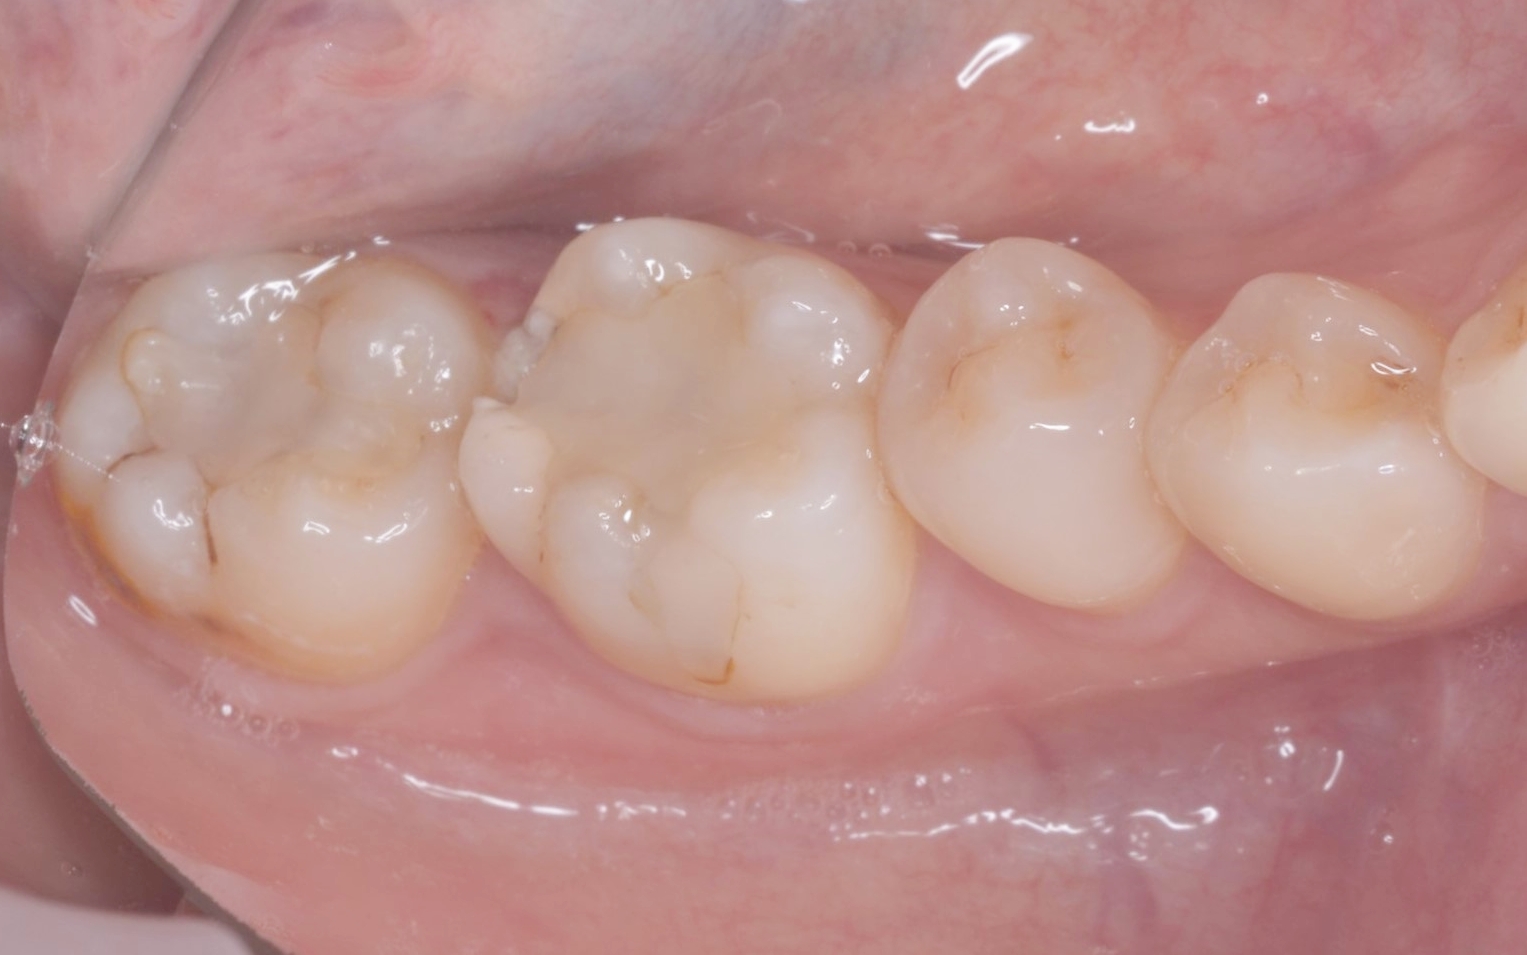

| カウンセリング | 拝見したところ、右下奥歯には歯槽骨(歯を支える骨)の近くまで進行している虫歯が認められました。通常の虫歯治療では、治療が困難な状態です。

このまま治療を行うと被せ物と歯の境目が歯茎の中に埋もれてしまい、結果として細菌が侵入しやすい状態になり、虫歯や歯周病のリスクが高まってせっかくの治療が長持ちしないおそれがあります。 以上のことから、歯の境目を歯茎の上に出す処置を行ってから、虫歯を治療する必要があると診断しました。 |

歯周外科手術を行いました。